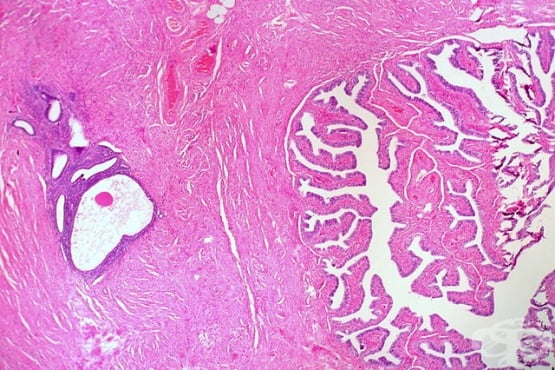

Ендометриоза Ендометриоза Симптоми на ендометриоза Симптоми на ендометриоза Ендометриоза Стадий 1 Стадий 2 Стадий 3 Стадий 4 Ехография - шоколадова киста (ендометриома) Лапароскопия на ендометриоза Лапароскопия на ендометриоза Хиатологично изследване на ендометриоза Ендометриоза на десния яйчник Аденомиоза на матката Ендометриоза и аденомиоза

ЕндометриозаЕндометриозаСимптоми на ендометриозаСимптоми на ендометриозаЕндометриозаСтадий 1Стадий 2Стадий 3Стадий 4Ехография - шоколадова киста (ендометриома)Лапароскопия на ендометриозаЛапароскопия на ендометриозаХиатологично изследване на ендометриозаЕндометриоза на десния яйчникАденомиоза на маткатаЕндометриоза и аденомиоза Ендометриоза